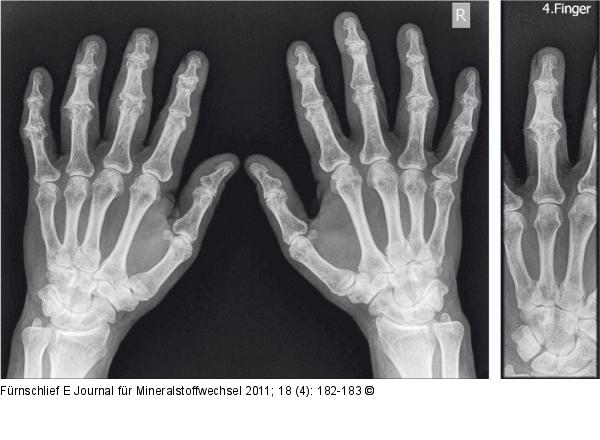

Abbildung 2a-b: Arthrose 11 Monate nach Therapiestart |